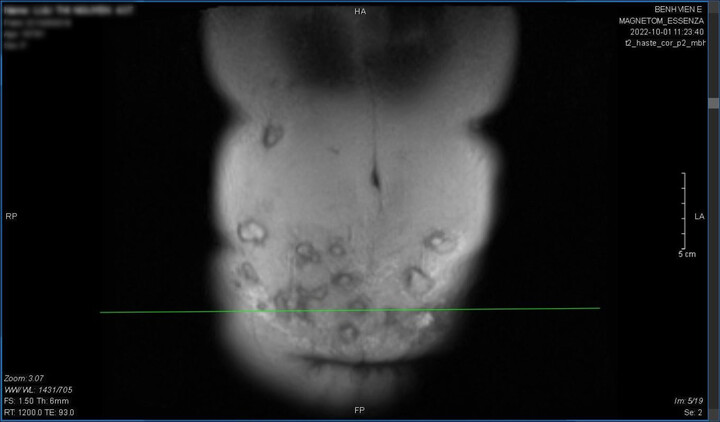

Theo đó, sau khi dùng dao sát hại bạn gái tại tiệm spa tối 10/10, Phan Trung Hòa đã được đưa đến cấp cứu tại Bệnh viện Đa khoa tỉnh Hải Dương. Các bác sĩ ca trực đã phẫu thuật xử lý vết thương tại vùng bụng và vùng cổ. Hiện nghi phạm Hòa đã được chuyển về hồi sức và có thể cai máy thở trong hôm nay ngày 11/10.